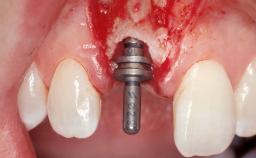

Late Placement of an Implant in a Maxillary Left Central Incisor Site

A 36-year-old female patient was referred for the replacement of the upper left central incisor (tooth 21), which had fractured. Although the tooth had been asymptomatic for many years, the crown began to loosen, at which time she presented to her dentist for an assessment. Teeth 21 and 22 had both been endodontically treated many years previously. She was a healthy individual and a non-smoker.

Abutment Type Customized

Placement Protocol Early or late implant placement

Loading Protocol Conventional or early